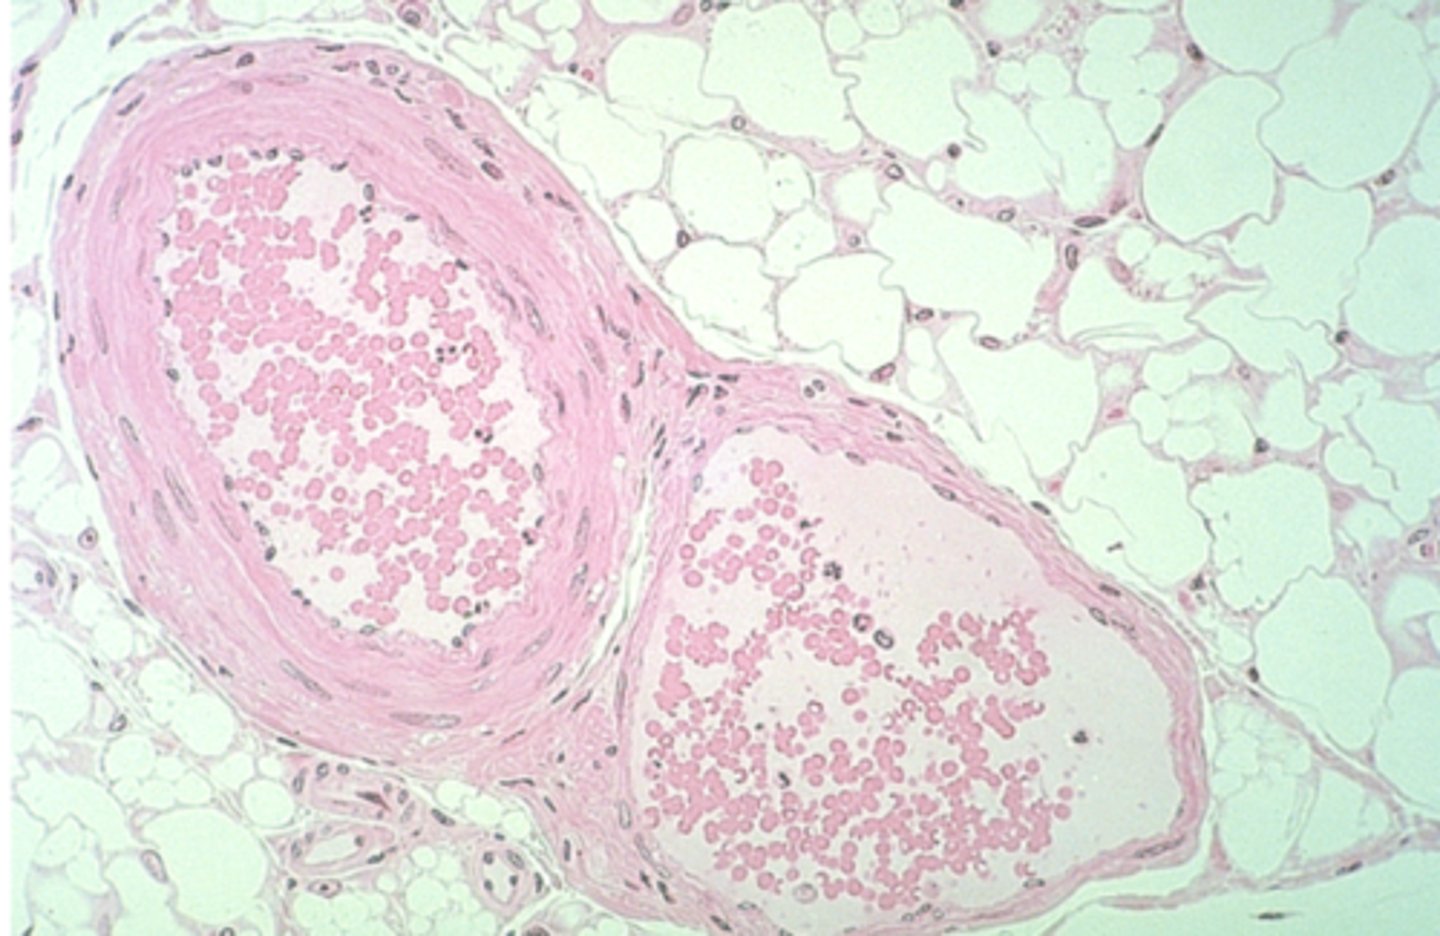

trachea

What is this?